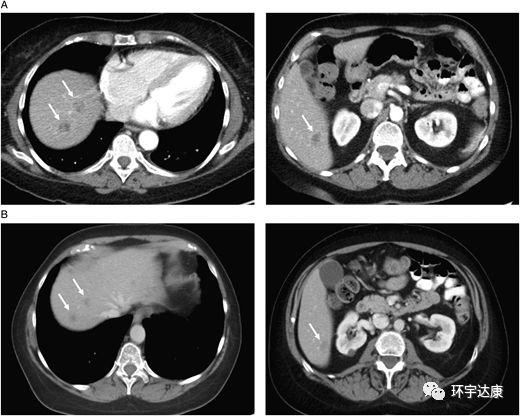

CT扫描:(A)治疗前(B)拉罗替尼治疗后

图2